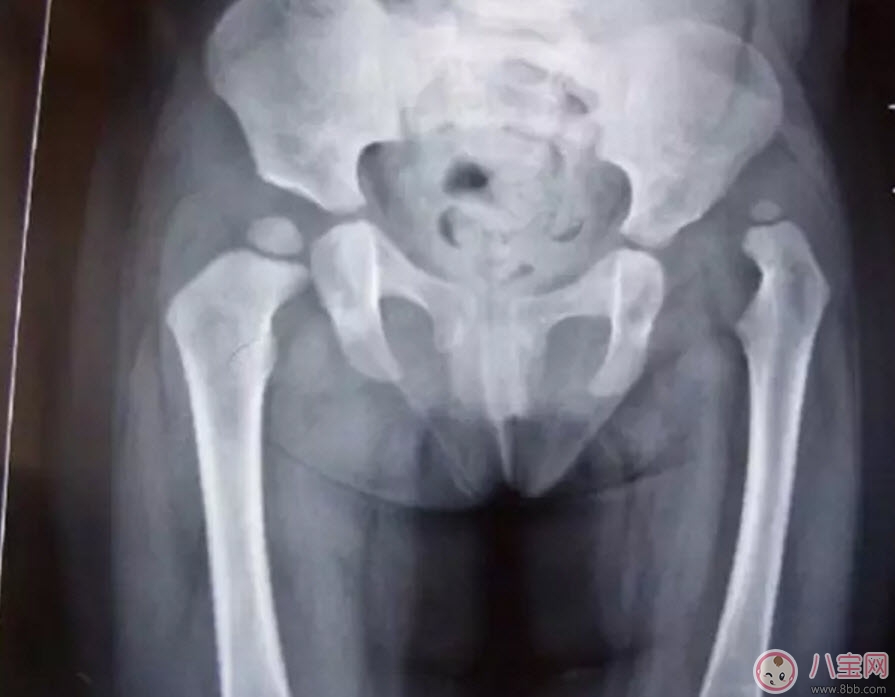

這是一個左側(cè)髖關(guān)節(jié)脫位的孩子的X光片。從這張片子上我們可以看到,孩子右側(cè)的髖關(guān)節(jié)是正常的,股骨頭和關(guān)節(jié)盂在一個水平位置上,但左側(cè)的股骨頭就完全離開了髖關(guān)節(jié)盂,跑到髖關(guān)節(jié)的上方去了,對于左側(cè)這種情況,我們就稱之為髖關(guān)節(jié)脫位。一般這種脫位都是先天的,或是孩子很小時候出現(xiàn)的,所以除了關(guān)節(jié)有脫位外,左側(cè)的股骨頭、股骨干、髖臼發(fā)育的也不正常,明顯比正常的一側(cè)要小。